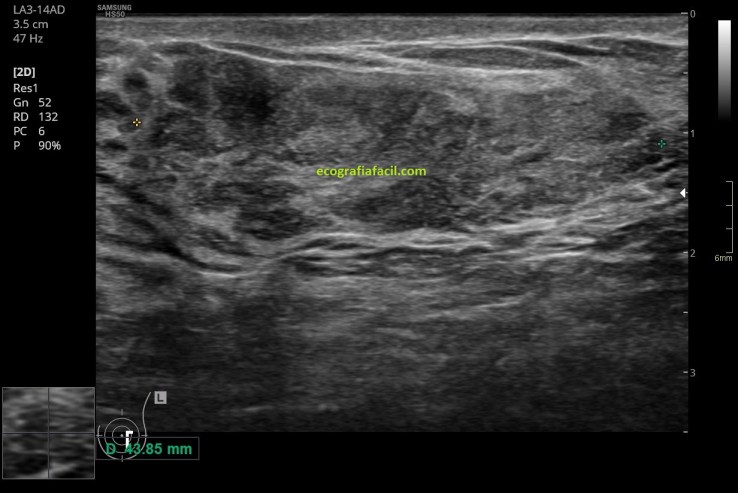

Internamente es, como he dicho, heterogénea (la paleta solo tiene grises, pero en la lesión son muchos y están muy mezclados), como puedes ver en la imagen 2, 3, 5 y 5, la vascularización, imagen 6, en este caso era muy escasa o nula. No hay alteración de los tejidos colindantes de la lesión y ésta, transmite bien.

En esta imagen número 3 puedes ver la relación del hamartoma con el tejido glandular periférico, su ecogenicidad y su transmisión sónica, elementos muy importantes a la hora de poder reconocer una estructura potencialmente «fea».

En la imagen 4 y 5 el estudio estándar, cortes axiales y longitudinales de la lesión.